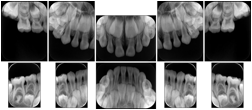

Intra-oral radiography typically involves acquisition of multiple images of various parts of the dentition. Many digital radiographic systems offer customized templates that are used for displaying the images in a study on the screen. These templates may also be referred to as mounts or view sets. The Structured Display Object represents a standard method of encoding and exchanging the layout and intended display of Structured Displays. A structured display object created in this manner could be stored with a study and exchanged with images to allow for complete reproduction of the original exam.

3. A dental provider wishes to capture a series of DICOM IO images for the patient’s dentition. The tooth morphology, teeth are divided into molars, premolars, canines and incisors, and a number of images for each jaw. The anatomic information was captured utilizing the triplet of schema. This standard code sequence is based on ISO 3950-2010, Dentistry - Designation system for teeth and areas of the oral cavity.

In most standard cases, images are oriented in structured layouts. These structured displays are useful to be shared between providers for reference purposes.

Table OO.1.1-1 shows structured display standard templates, where Viewset ID is based on the Japanese Society for Oral and Maxillofacial Radiology (JSOMR) classification provided by JIRA (Japan Medical Imaging and Radiological Systems Industries Association, www.jira-net.or.jp). Expected or typical teeth to be imaged location, region and designation codes are based on ISO 3950-2010, Dentistry - Designation system for teeth and areas of the oral cavity. For all the hanging protocols listed in OO.1.1-1, the value to use for Hanging Protocol Creator (0072,0008) is "JSOMR" and the value to use for Hanging Protocol Name (0072,0002) does not include "JSOMR" (e.g., "DL-S001A", not "JSOMR DL-S001A").